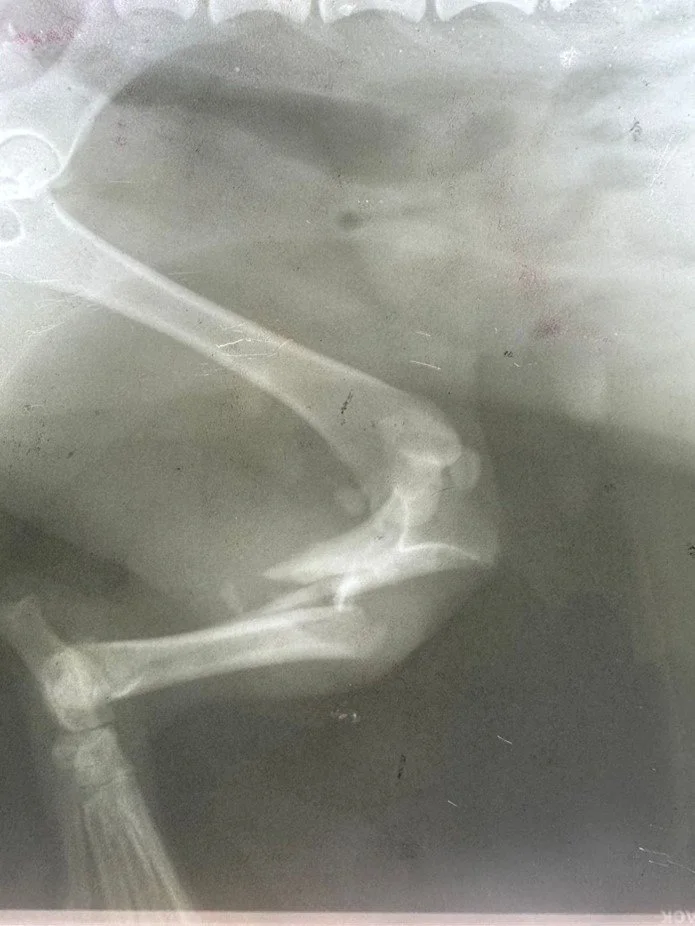

One rescued dog that illustrates the impact of this work is Alisa. Found in the village of Sarata with a broken leg, head wounds and other injuries, Alisa was brought to our partner Zhanna and taken to several clinics before one agreed to operate. After months of treatment and rehabilitation she began walking, then running, and is now in foster care with a pathway to adoption. Alisa’s recovery shows how targeted funding for emergency treatment saves lives — and, with luck, returns animals to loving homes.

Alisa after the op